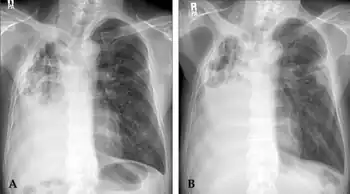

Radiographic findings with M. xenopi pulmonary disease are variable but most often include upper lobe cavitary abnormalities similar to tuberculosis.